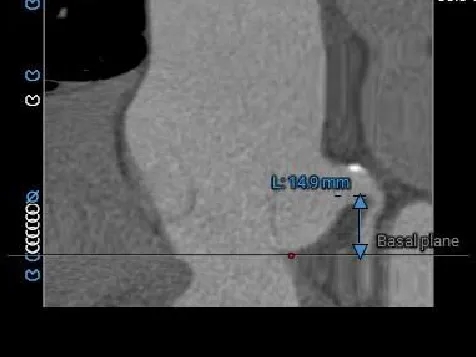

LCA Height

RCA Height

LCA & Leaflet

RCA & Leaflet

冠脉开口高度可,瓣叶不长,冠脉阻挡风险不高